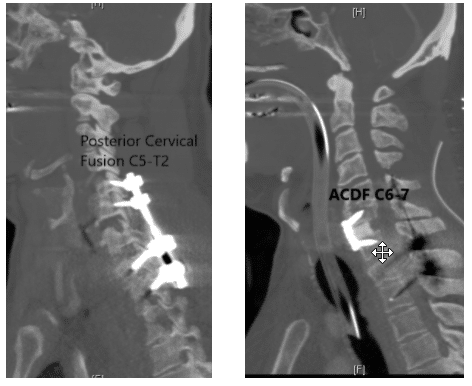

To regain the stability back the spine was fused from the front as well as from the back using plate, screw and rods. Anterior Cervical Discectomy and Fusion (ACDF) C6-7 with Posterior Spinal Fusion C5-T2 was performed.

Posterior Spinal Fusion C5-T2